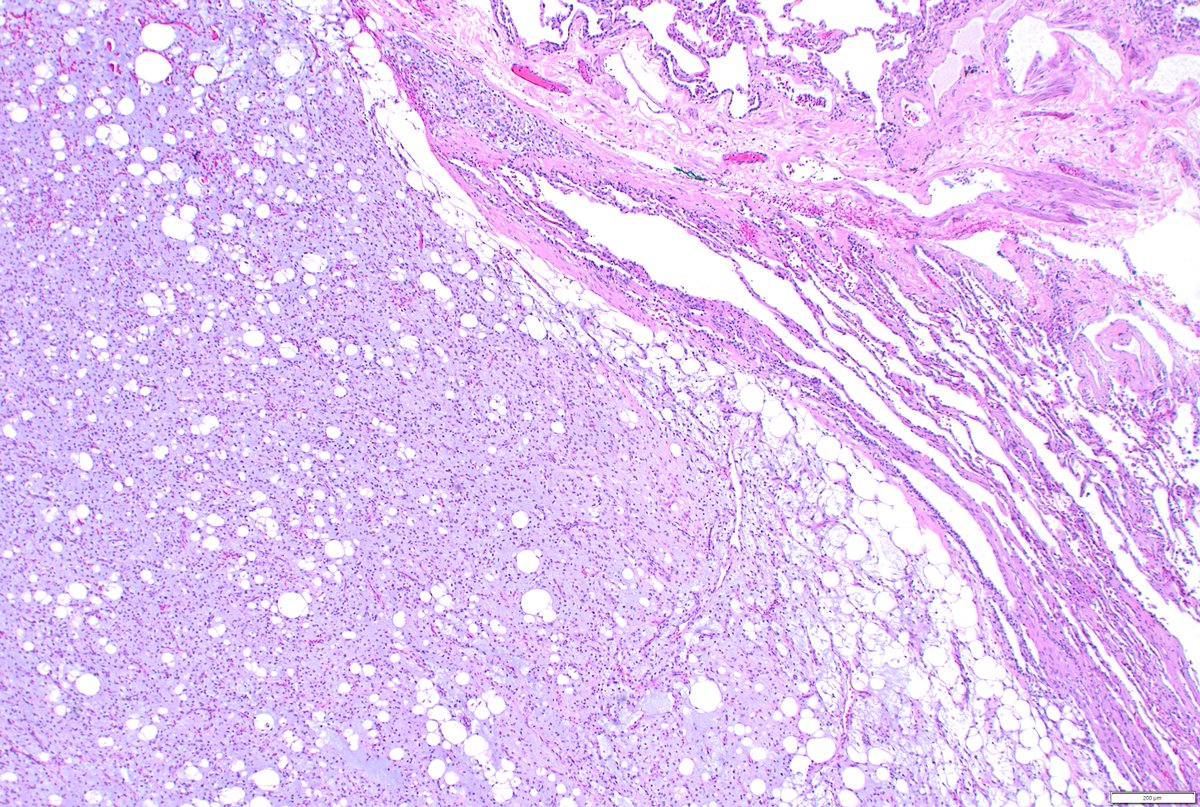

Just out in AJSP – a paper from our group describing a MAJOR new oddity. Tumors that normally arise in the jaw from tooth🦷precursors (ameloblastoma) – but as lung primaries 🫁! This was a neat collaboration b/w MSKCC, Mayo and UTSW where these cases were encountered independently, and we put our heads together with the help of original contributors and fellows to tackle this puzzle. Time will tell if these are truly exceptional or have been underrecognized. journals.lww.com/ajsp/fulltext/… @JLHornick @ENTpathology @MSKPathology @PulmPathSoc @yro854 @thoracicpath @Path_Matt @SansanoValero @AndreMo77438628